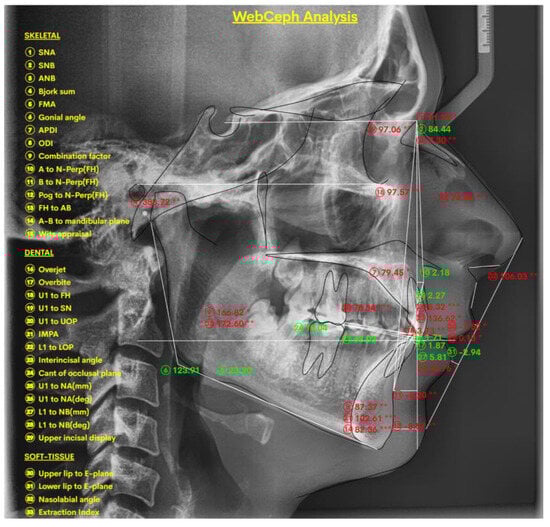

- Mahto, R.K.; Kafle, D.; Giri, A.; Luintel, S.; Karki, A. Evaluation of Fully Automated Cephalometric Measurements Obtained from Web-Based Artificial Intelligence Driven Platform. BMC Oral Health 2022, 22, 132. [Google Scholar] [CrossRef]

- Yassir, Y.A.; Salman, A.R.; Nabbat, S.A. The Accuracy and Reliability of WebCeph for Cephalometric Analysis. J. Taibah Univ. Med. Sci. 2022, 17, 57–66. [Google Scholar] [CrossRef]

- Katyal, D.; Balakrishnan, N. Evaluation of the Accuracy and Reliability of WebCeph–An Artificial Intelligence-Based Online Software. APOS Trends Orthod. 2022, 12, 271–276. [Google Scholar] [CrossRef]

- Natrajan, K.; Selvarajan, K.; Geevee, A.; Elango, E.; Sankar, H.; Krishnan, P. Accuracy and Reliability of WebCeph on Posteroanterior Cephalogram—A Retrospective Study. J. Contemp. Orthod. 2024, 8, 491–495. [Google Scholar]